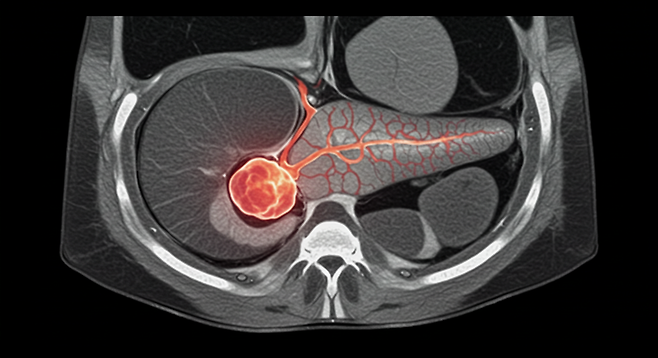

췌장은 우리 몸에서 소화 효소와 호르몬(인슐린)을 생산하는 중요한 장기입니다. 췌장염은 이러한 췌장에 염증이 생기는 질환으로, 초기에는 증상이 미미하여 간과하기 쉽습니다. 하지만 방치하면 심각한 합병증을 초래할 수 있으므로, 초기 증상을 인지하고 적절한 대처를 하는 것이 중요합니다.

- 즉시 병원 방문: 소화기내과 전문의에게 진료를 받고 정확한 진단을 받아야 합니다. 혈액 검사, 복부 CT, MRI 등의 검사를 통해 췌장염 여부와 원인을 확인할 수 있습니다.